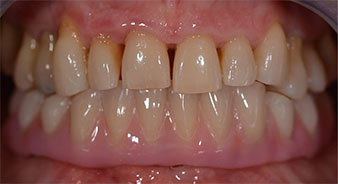

Following the time required for the osseointegration, the final impression of the implants could be performed and the final denture produced accordingly (Fig. 19 and 20). At this point, the dentist and patient were able to decide together whether to use a ceramic or acrylic veneer and a zirconium or metal framework. In this case, Dr. Pascu’s team decided on an acrylic veneer based on the unclear prognosis for the maxillary dentition and the fact that tooth 24 is elongated. This type of veneer is generally considerably easier to adapt and can thus be subsequently altered to reflect the new situation in the maxilla.

Osseointegration

Fig. 19

Implants

Fig. 20